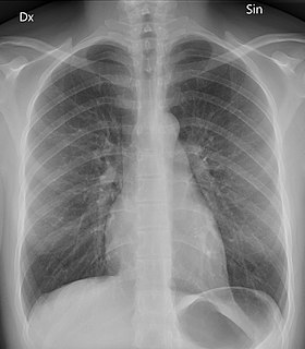

imagepathを書き換えます。ここでは、Wikipediaの正常なレントゲンの画像を使います。

chest.jpgという名前で保存しました。https://en.wikipedia.org/wiki/Chest_radiograph#/media/File:Normal_posteroanterior_(PA)_chest_radiograph_(X-ray).jpg

python inference.py \ --weightspath models/COVIDNet-CXR4-A \ --metaname model.meta \ --ckptname model-18540 \ --imagepath /tmp/share/chest.jpg結果は…

Prediction: COVID-19 Confidence Normal: 0.000, Pneumonia: 0.000, COVID-19: 1.000おっと、なんと 100% COVID-19であるという判定になってしまいました!

これは明らかな間違いです。

このように、このモデルの精度はあまり高くありません。私が試してみた範囲でも、かなり高い確率でCOVID-19と誤判定する傾向がありました。deep learningを利用した画像判別器が間違えることは多々あるということです。AIという言葉はときどき独り歩きしていることがありますが、画像分類器(通称AI)は単なる道具でありますから、むやみに盲信したり怖がったりする必要はありません。

https://en.wikipedia.org/wiki/Chest_radiograph#/media/File:Normal_posteroanterior_(PA)_chest_radiograph_(X-ray).jpg

Geographic severity: 0.293 Geographic extent score for right + left lung (0 - 8): 2.341 For each lung: 0 = no involvement; 1 = <25%; 2 = 25-50%; 3 = 50-75%; 4 = >75% involvement. Opacity severity: 0.242 Opacity extent score for right + left lung (0 - 6): 1.450 For each lung: 0 = no opacity; 1 = ground glass opacity; 2 =consolidation; 3 = white-out.こちらは、浸潤はほとんどないか、肺スリガラス状陰影(Ground Glass Opacity) がわずかにあるという判定になったようです。COVID-19の判定は完全に誤っていましたが、重症度判定はかなり低く判定されているようです。傾向としては、大きく間違っていないかもしれません。